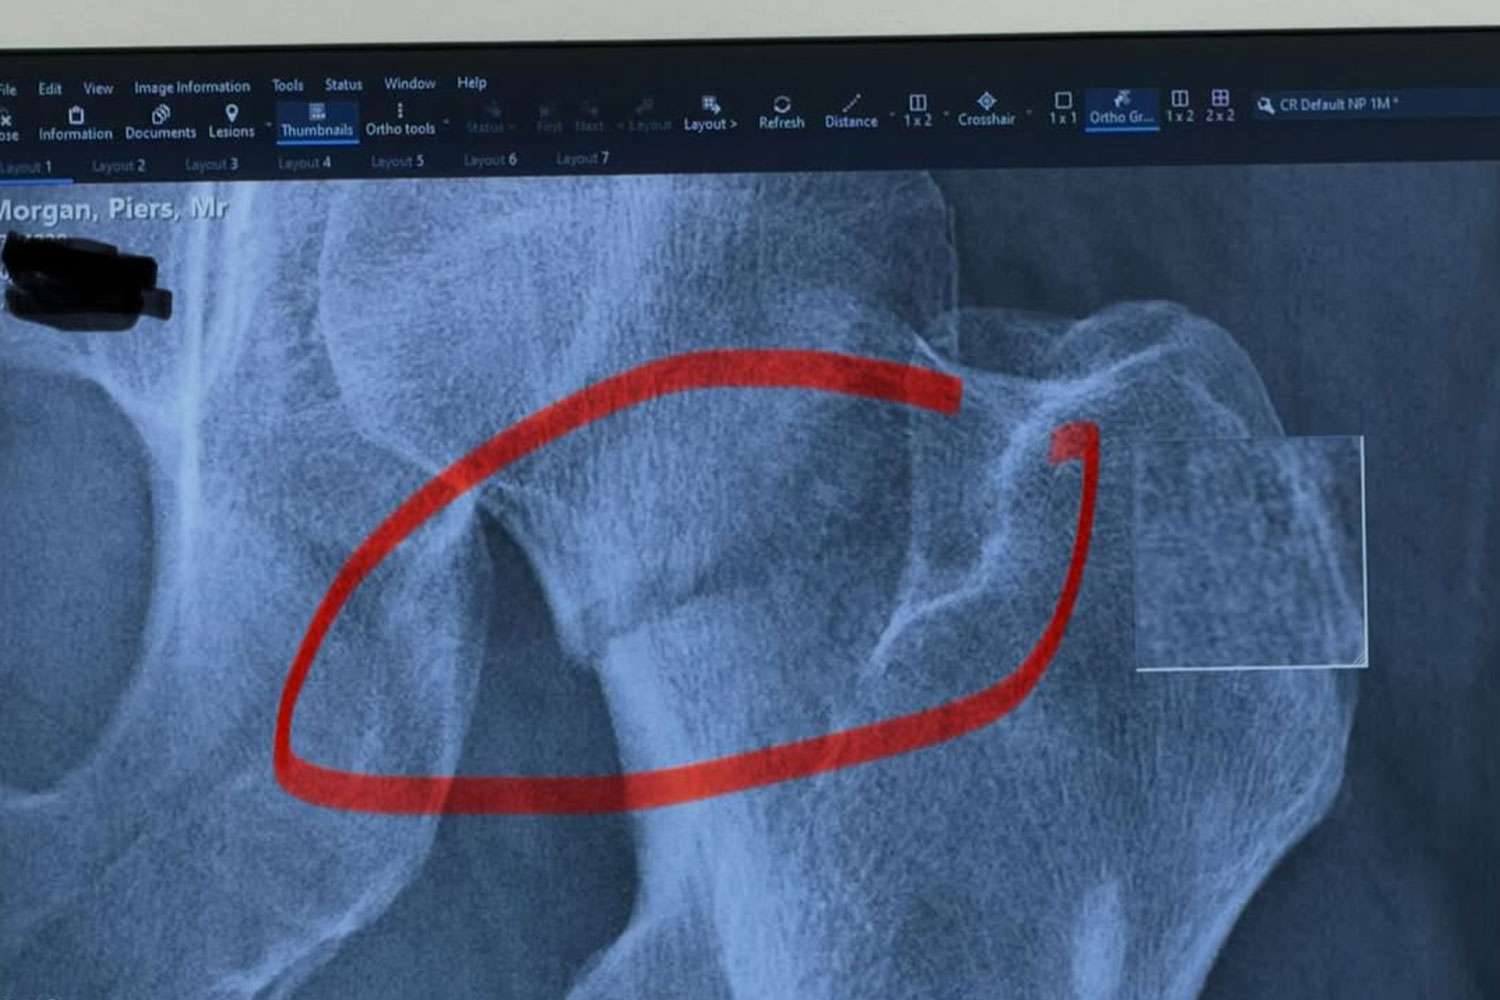

Наряду с селфи на больничной койке Морган также поделился изображением рентгеновского снимка после падения.

На этой фотографии он нарисовал красный кружок поверх черно-белого изображения, подчеркнув свою травму.